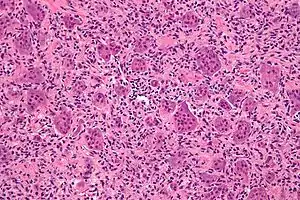

Micrograph of a giant-cell tumor of bone showing the characteristic giant cells, H&E stain

High magnification micrograph of giant cells in a giant-cell tumor of bone, H&E stain

The diagnosis of giant-cell tumors is based on biopsy findings. The key histomorphologic feature is, as the name of the entity suggests, (multinucleated) giant cells with up to a hundred nuclei that have prominent nucleoli. Surrounding mononuclear and small multinucleated cells have nuclei similar to those in the giant cells; this distinguishes the lesion from other osteogenic lesions which commonly have (benign) osteoclast-type giant cells. Soap-bubble appearance is a characteristic feature.